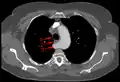

Images

Aberrant subclavian artery at axial CT-scan. (1) trachea, (2) esophagus, (3) Aberrant subclavian artery.